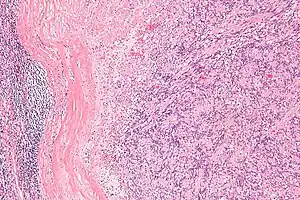

IPMs are diagnosed by examination of the tissue by a pathologist. They have a rim of peripheral lymphoid tissue (remnant of a lymph node) and consist of spindle cells with nuclear palisading. Red blood cell extravasation is common and blood vessels surrounded by collagen with (fine) peripheral spokes (amianthoid fibers) are usually seen.[3]

Immunostains for smooth muscle actin and cyclin D1 are characteristically positive. The main histologic differential diagnosis is schwannoma.

Intranodal palisaded myofibroblastoma with a thin rim of residual lymph node -

Low mag.Intranodal palisaded myofibroblastoma -